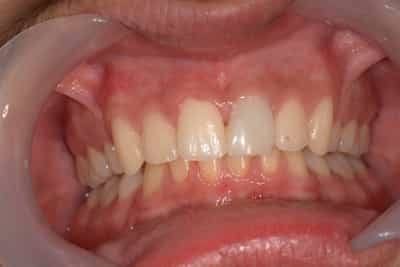

Cas numero 1 :

Situation Initiale

Etude du cas et proposition

Cas terminé